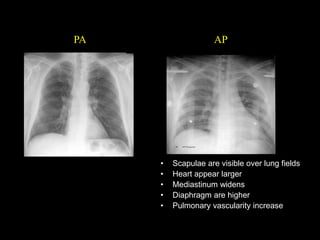

PA or AP view

PA

• Scapulae are visible over lung fields

• Heart appear larger

• Mediastinum widens

• Diaphragm are higher

• Pulmonary vascularity increase

AP